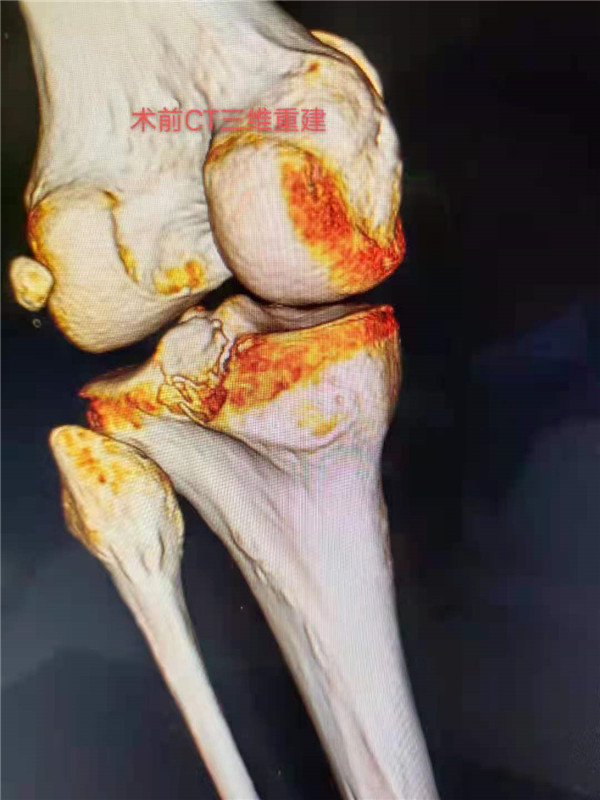

患者李某,今年37岁,因几日前跨越障碍物时不慎摔倒,左膝着地,当即觉得左膝疼痛难忍、活动受限。于12月1日入市三院就诊,入院后查左膝正侧位片、左膝CT三维重建等检查:提示后交叉韧带止点撕脱性骨折。经骨一科主任邵建敏和副主任医师徐军志反复查阅相关资料及科室病例讨论后,充分与患者及家属沟通并征得同意后,建议行改良小切口下行止点重建术。徐军志副主任医师于12月2 日在腰硬联合麻醉下为患者行左膝后叉止点撕脱性骨折复位内固定止点重建术,术后切口长约3CM。术后患者无不适感,症状明显改善,疼痛明显缓解,并于术后2天出院。